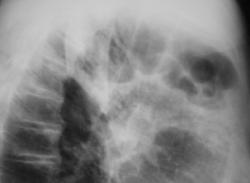

Иллюстрации 2 и 3. Томограммы.

Иллюстрация 4. Томограмма – срез 5 см. Высказано предположении о наличии хронической пневмонии в задне-базальных сегментах.

Иллюстрации 5. На срезе 10 см. справа в корне создается впечатление «наличия увеличенных бронхопульмональных лимфатических узлов» и некоторое «сужение промежуточного бронха».

Было высказано предположение о наличии неопластического процесса в области промежуточного бронха справа, нарушении бронхиальной проходимости справа, с учетом гиповентиляции правого легочного поля, наличии хронической пневмонии в заднее-базальных сегментах правого лёгкого.